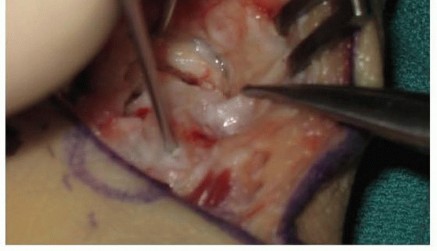

The harvested graft is meticulously shaped on the back table using a rongeur or a fine burr to perfectly match the dimensions of the scaphoid defect. The graft is then press-fit into the volar void with the cortical surface facing volarly to act as a structural buttress, and the cancellous portion facing the medullary canal to promote osteogenesis. The joysticks are relaxed, allowing the native ligamentous tension to compress the scaphoid fragments against the newly inserted wedge graft, locking it securely in place.

Image

Rigid internal fixation is then achieved. A 0.035-inch guidewire for the cannulated headless compression screw is introduced from the distal scaphoid tubercle, directed proximally, dorsally, and ulnarly, aiming for the absolute central axis of the proximal pole. The trajectory is verified in multiple planes using intraoperative fluoroscopy. Achieving a central position in the proximal pole is statistically correlated with higher union rates and superior biomechanical pull-out strength.

Once the guidewire trajectory is confirmed, the length is measured. The outer cortex of the distal scaphoid is over-drilled to allow the screw head to countersink beneath the articular cartilage. The appropriate length headless compression screw is then advanced over the wire. As the variable pitch threads engage, the surgeon will visually and fluoroscopically observe robust compression of the distal fragment, the intercalated wedge graft, and the proximal fragment into a single, rigid construct.

The final step involves a rigorous fluoroscopic examination to ensure anatomical reduction, proper screw length without joint penetration, and solid compression. The joysticks and guidewire are removed. The volar capsule is meticulously repaired using 3-0 or 4-0 absorbable sutures to restore radiocarpal stability. The pronator quadratus is allowed to fall back over the radial donor site, and the FCR sheath and skin are closed in layers. A sterile dressing and a well-molded volar thumb spica splint are applied before the tourniquet is deflated.